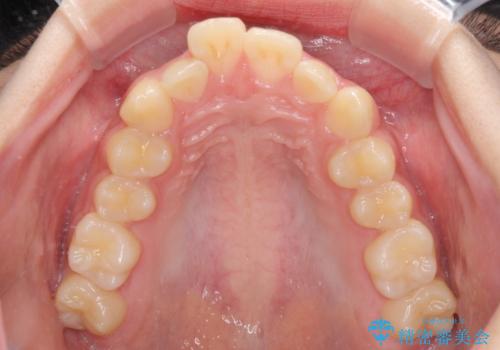

下の前歯が隠れてしまうほど深い咬み合わせ 高校生のインビザライン矯正治療

- 前歯の叢生と深い咬み合わせを気にして来院された患者様です。

奥歯の咬み合わせと深い咬み合わせを改善した後、インビザラインで歯列を整えることとしました。